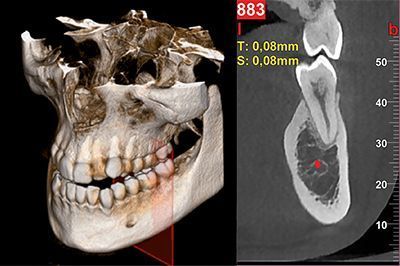

NewTom GO генерирует выдающиеся объемные изображения и для каждого FOV в диапазоне от 6х6 до 10х10 см. Выбор из 3 протоколов позволяет адаптировать требуемую дозу рентгеновского излучения к конкретным потребностям: от очень низкой для быстрого сканирования, необходимого при последующих хирургических проверках, до регулярной для планирования лечения, до очень высокого уровня детализации для анализа микроструктур.Минимальная доза, максимальное диагностическое качество

NewTom GO создаёт выдающиеся объемные изображения для каждого поля обзора, от 6*6 до 10*10 см. Выбор из 3 протоколов позволяет устанавливать дозу излучения, требуемую для конкретной задачи: от очень низкой для быстрого сканирования при хирургическом наблюдении, средней для планирования лечения, до очень высокого уровня детализации для анализа микроструктур.